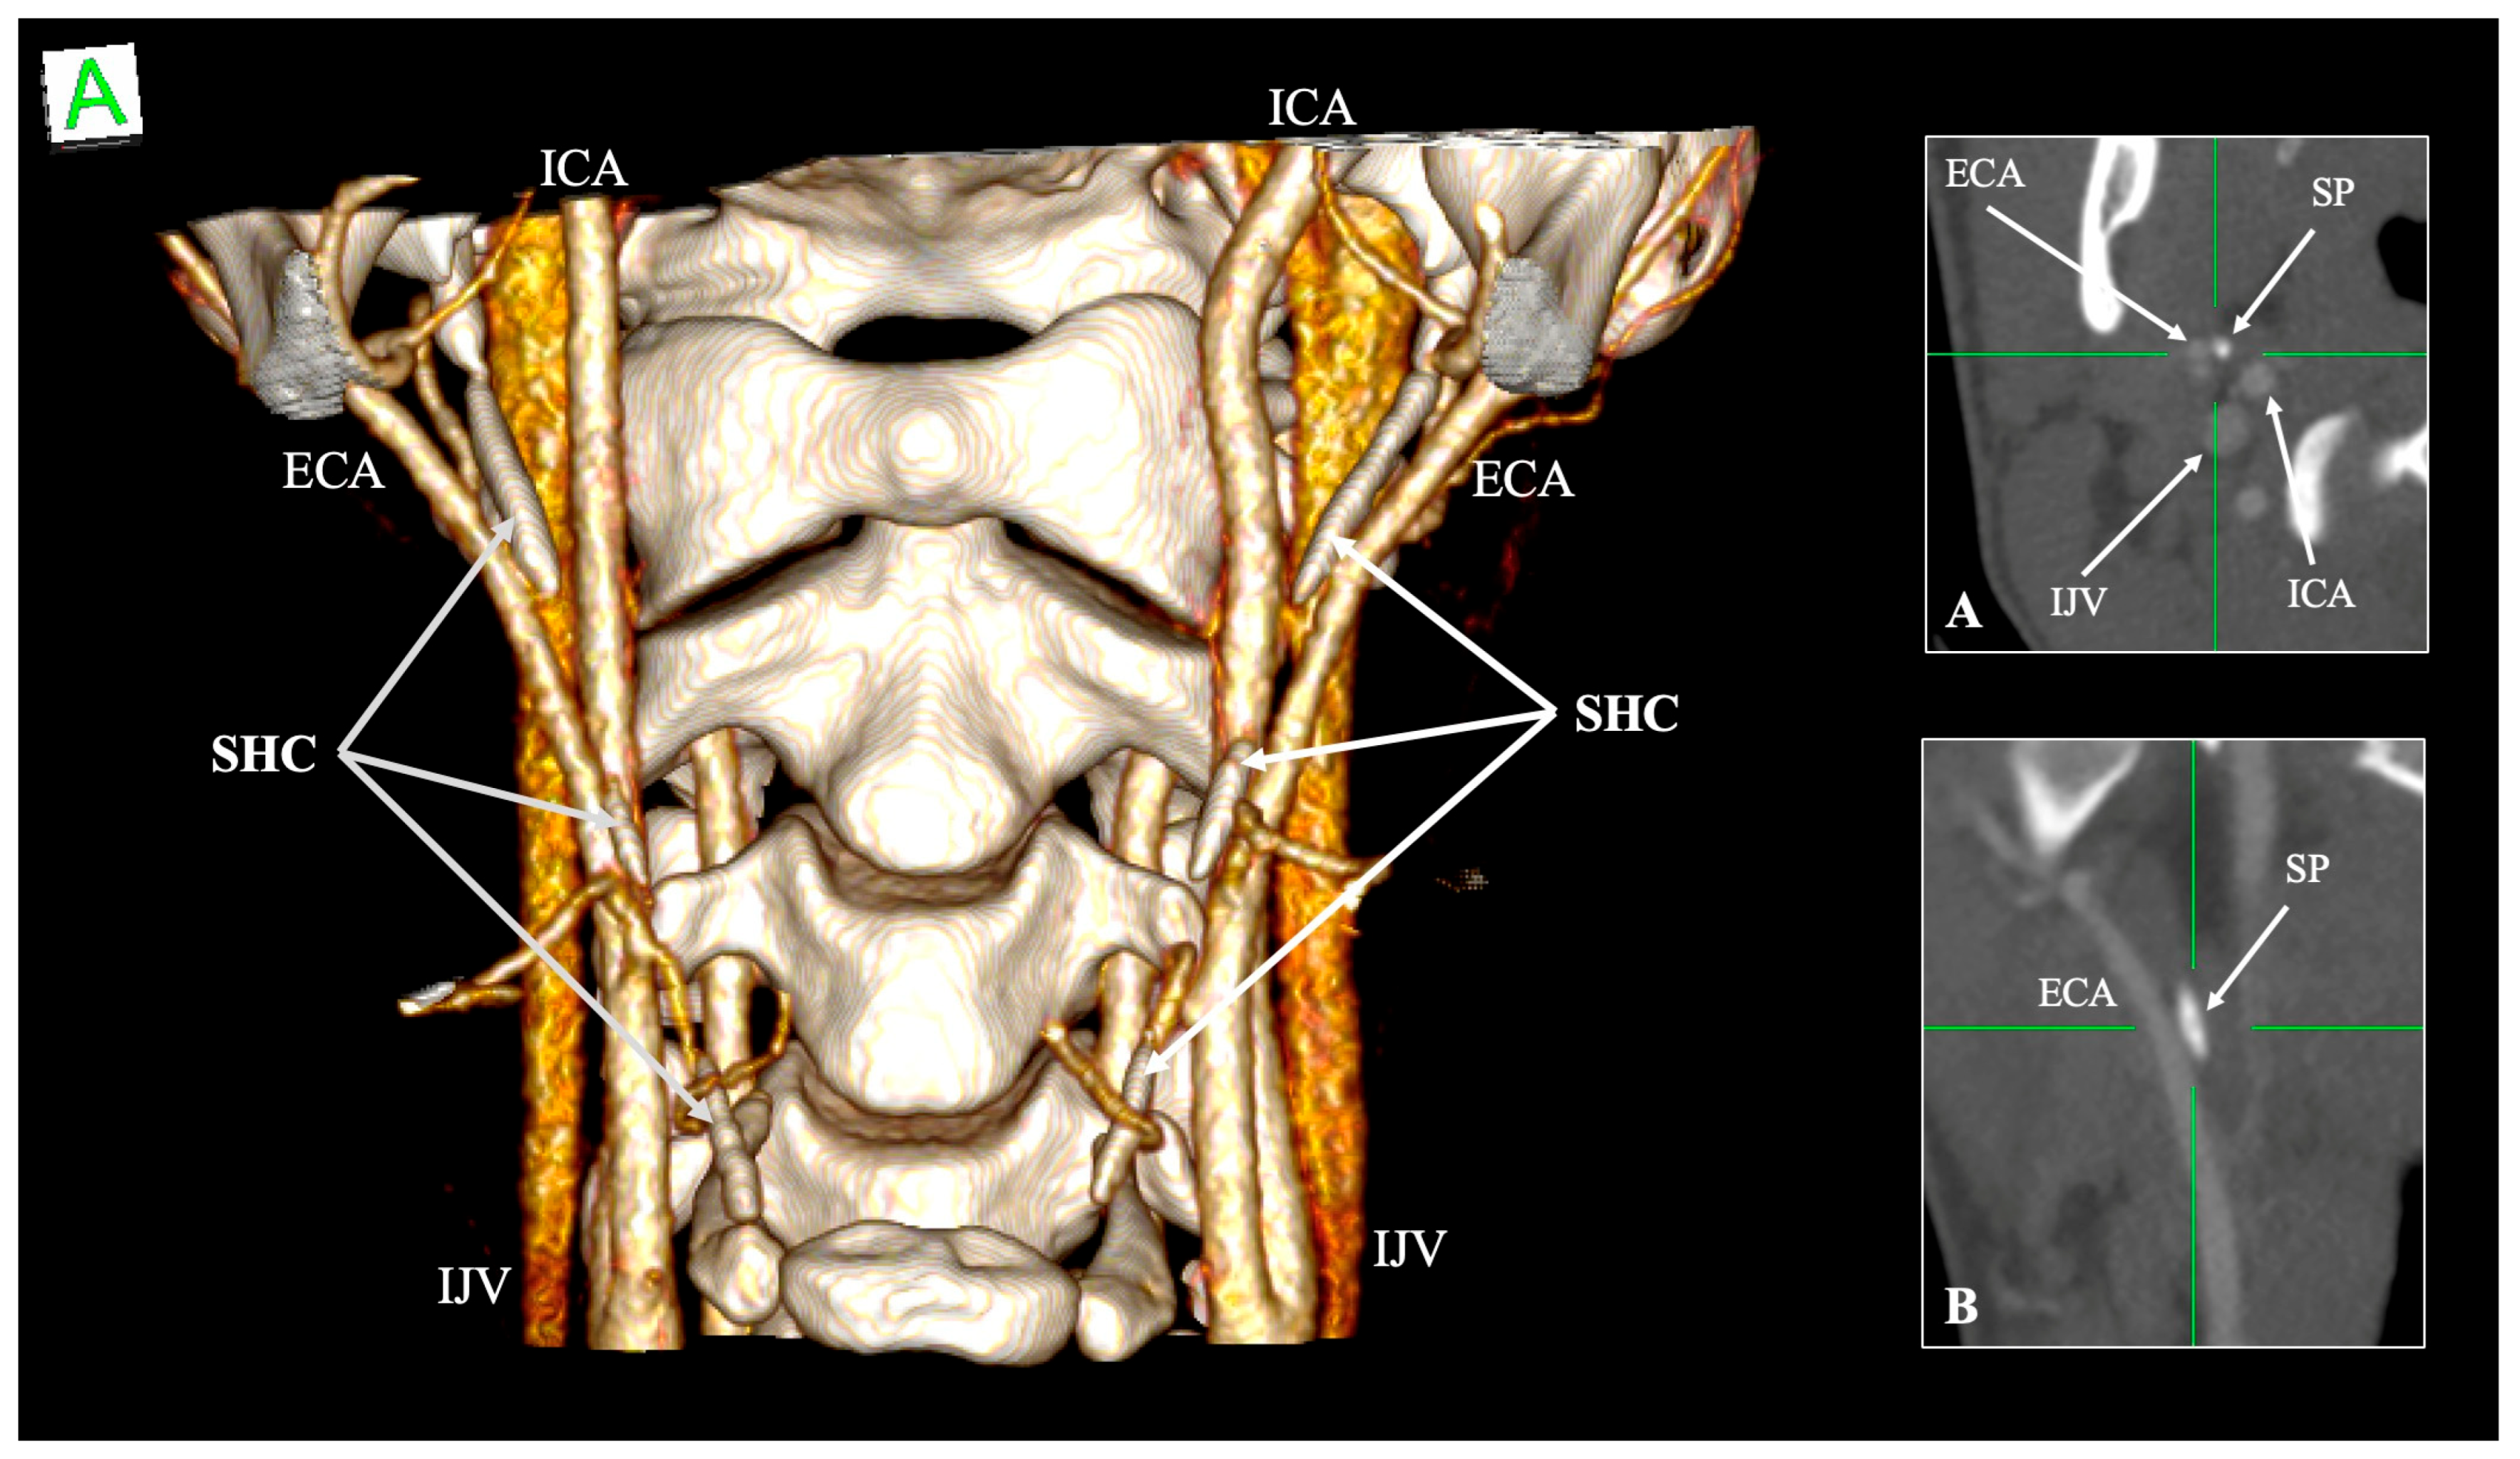

| SHC | Stylohyoid complex |

| Internal carotid artery (ICA) | Medial to SP, ascends branchless to the skull base | Tortuosity, kinking, coiling; reduced ICA–SP distance; direct bony contact | Risk of dissection, ischemic stroke, and hemorrhage during pharyngeal surgery | Paulsen et al. [14]; Renard et al. [47]; Raser et al. [45]; Amorim et al. [46] |

| External carotid artery (ECA) | Anterolateral to SP; gives facial and pharyngeal branches | Retro-styloid course (~9–12%) | Altered surgical corridor; potential compression or irritation | Karangeli et al. [17]; Calotă et al. [50] |

| Internal jugular vein (IJV) | Posterolateral to SP within the carotid sheath | Compression between SP and C1 transverse process (“jugular nutcracker”) | Intracranial hypertension, venous congestion, hemorrhage | Triantafyllou et al. [48] |